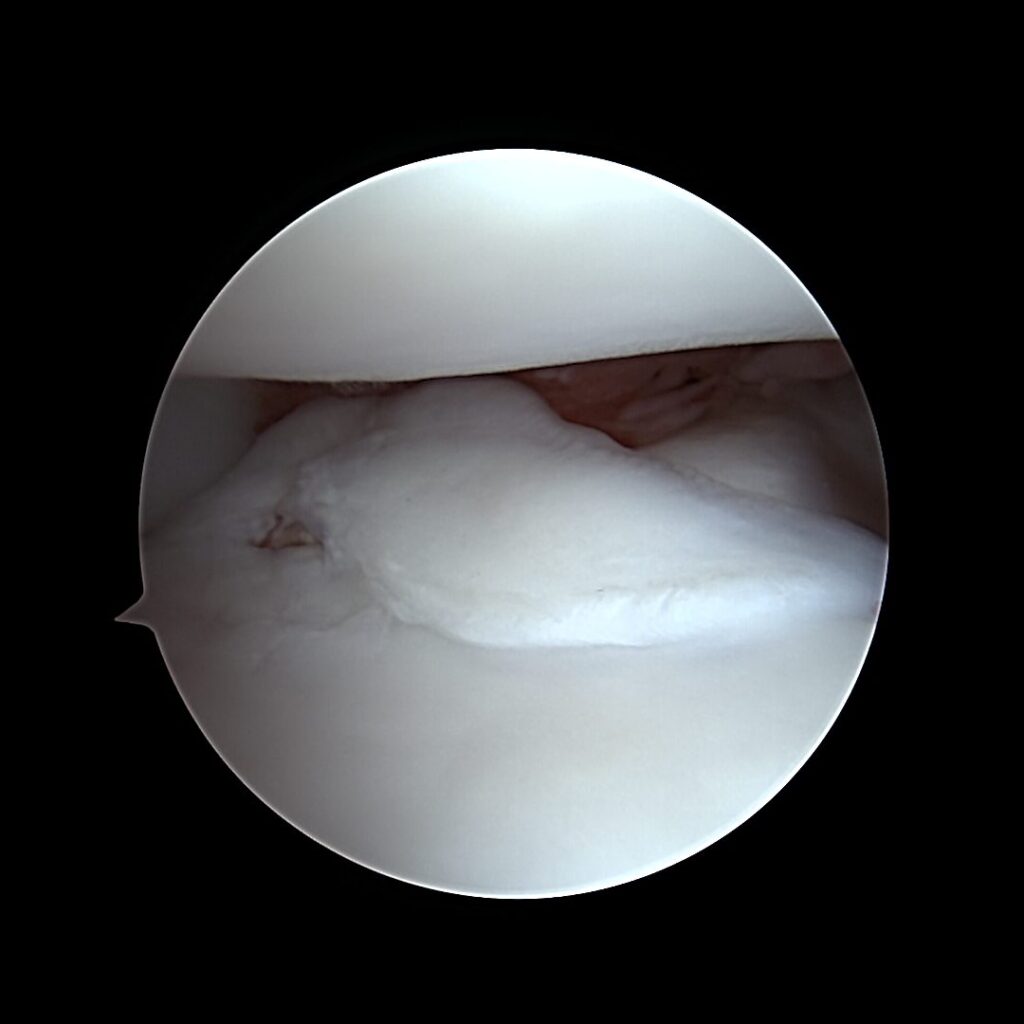

Arthroscopy

We have new Arthrex 4HD arthroscopy stacks which allows our surgeons to see inside joints with amazing clarity and to operate very precisely. Arthroscopy is commonly used in the shoulder, elbow and stifle (knee) joints